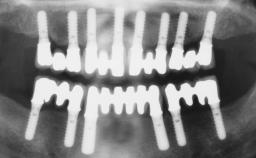

A 35-year-old Caucasian female presenting with advanced periodontal disease involving both the maxillary and the mandibular dentition was referred for evaluation. The patient, a non-smoker in good general health, requested treatment for recurrent periodontal abscesses, tooth mobility, and discomfort during chewing, as well as restoration of her missing teeth with a fixed prosthesis to improve mastication and esthetics. All residual maxillary teeth exhibited plaque deposits, deep pockets, bleeding on probing, and class III mobility and were evaluated as hopeless. All residual mandibular teeth except tooth 37 could be maintained after periodontal therapy.